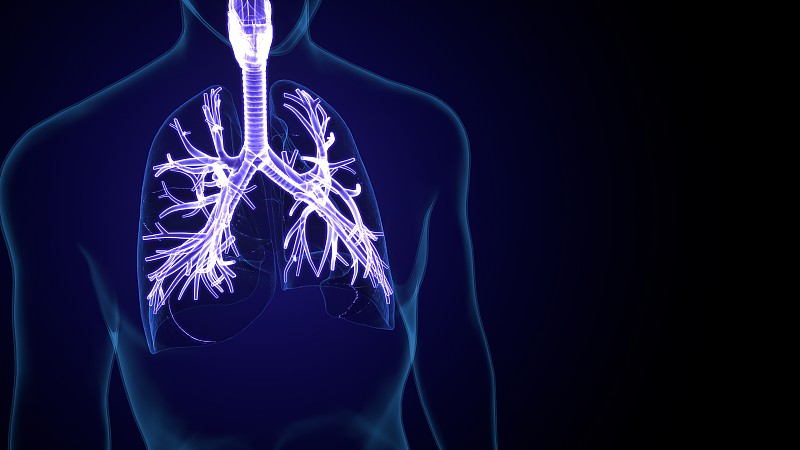

人体呼吸系统肺解剖学详情

JPG

人体呼吸系统肺解剖学详情

JPG

人体呼吸系统肺解剖学详情

JPG

人体呼吸系统肺解剖详情

JPG

人体呼吸系统肺解剖详情

JPG

人体呼吸系统肺解剖学详情

JPG

人体呼吸系统肺解剖学详情

JPG

人体呼吸系统肺解剖学详情

JPG

胸腔前视图中的肺详情

JPG

人体呼吸系统肺解剖学详情

JPG

人类肺部的科学背景详情

JPG

人体呼吸系统肺解剖学详情

JPG

人体呼吸系统肺解剖详情

JPG

人体呼吸系统肺解剖学详情

JPG

人体呼吸系统肺解剖学详情

JPG

人体肺的示意图详情

JPG

医疗插图详情

JPG

人体呼吸系统肺解剖详情

JPG

人体呼吸系统肺解剖详情

JPG

人体呼吸系统肺解剖学详情

JPG

人类呼吸系统详情

JPG